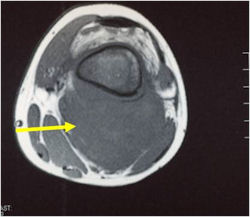

- Long Bones – Most common

- Femur: Single most common site

- Humerus

Radiographic Presentation

- Permeative or moth eaten bone destruction

- Soft Tissue Mass in 90% of of cases

- Limb sparing surgery whenever feasible unless there will be a large leg length discrepancy that can not be accomodated for with surgery

- Rarely ever an amputation since Ewing sarcoma are sensitive to radiation